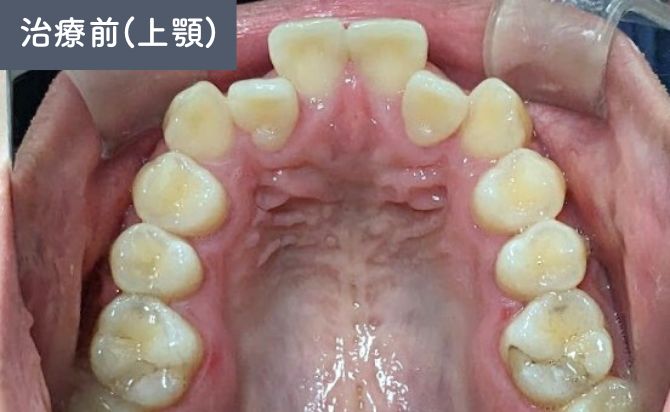

歯並びの変化(上)

上顎1番の前方位が確認され、口元の突出感に影響していました。また、上顎2番の舌側傾斜があり、歯列全体の並びにも不均衡がみられました。

さらに、下顎歯列弓が方形型であることから、上下のアーチ形態のバランスが整っておらず、前歯部の噛み合わせにも改善の余地があると判断しました。

IPR(歯間削合)を適宜行い、スペース確保を図りながらアーチを整えていく計画としました。アタッチメントを併用して歯の移動方向を細やかにコントロールしています。

治療終了時には、患者様が気にされていた上顎1番の突出が軽減され、前歯の位置が適正化しました。上顎2番の舌側傾斜も改善され、左右のバランスが整った歯列アーチが得られています。

右側3番の切端咬合も改善し、犬歯誘導が適切に働く咬合状態となりました。上下のアーチ形態のバランスも改善し、見た目だけでなく、機能的にも安定した咬合が確立されています。